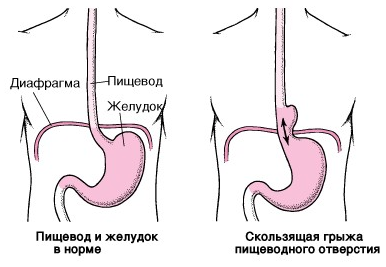

Скользящая грыжа пищеводного отверстия диафрагмы

Грыжа пищеводного отверстия диафрагмы (ГПОД) — хроническое заболевание, при котором брюшной отдел пищевода и часть желудка смещаются в грудную полость через патологически расширенное пищеводное отверстие диафрагмы. При локализации кардии выше диафрагмального отверстия речь идет о скользящей грыже (аксиальной) — наиболее часто встречающейся форме ГПОД. Периодически смещенная часть желудка возвращается в свое нормальное положение, симптомы при этом исчезают.

Под действием различных факторов связки, фиксирующие желудок и пищевод, растягиваются, соотношение между пищеводом и желудком изменяется. В результате часть желудка и пищевода, чаще при изменении положения тела, свободно перемещаются через расширенное отверстие диафрагмы в полость грудной клетки и возвращаются обратно.

При этом полностью сглаживается угол Гиса — в норме это острый угол, образованный при впадении пищевода в желудок. Это анатомическое образование препятствует обратному забросу пищи из желудка в пищевод. В результате изменения угла Гиса и нарушения функции нижнего сфинктера пищевода содержимое желудка или желчь свободно попадают в пищевод. Обладая агрессивными свойствами, содержимое действует на слизистую оболочку, в результате чего развивается воспалительный процесс в пищеводе — рефлюкс-эзофагит.